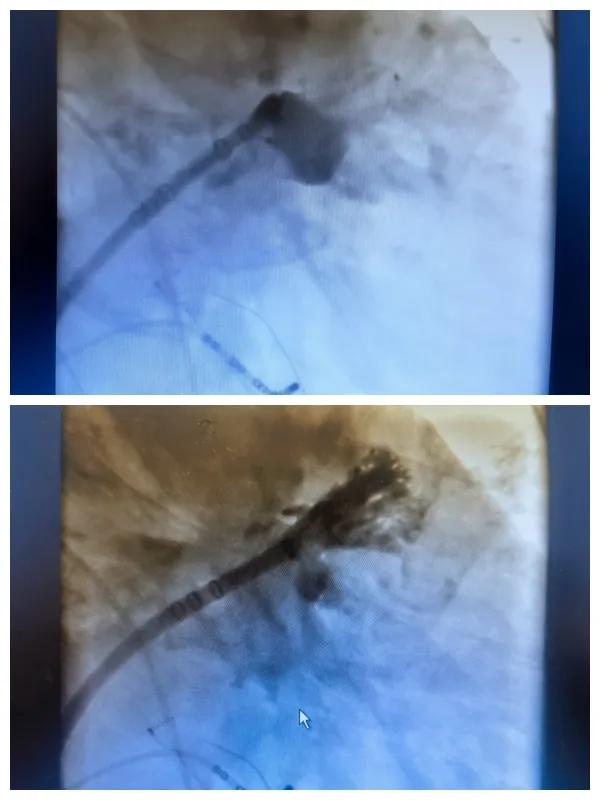

6月26日,市二院成功為一名老年房顫患者實施了房顫射頻消融術(shù)+左心耳封堵WM FLX一站式介入治療,標志著醫(yī)院在心律失常介入治療領域邁出了嶄新的一步,開啟了新的治療篇章。

本次手術(shù)特邀我國著名心血管內(nèi)科專家、河南省胸科醫(yī)院黨委書記袁義強及血管內(nèi)科七病區(qū)主任黃瓊教授蒞臨指導,市二院院長王瑾帶領心血管內(nèi)科電生理等專家團隊緊密合作,一次性解決了患者房顫、血栓兩大困擾,也使患者告別了終身服用抗凝藥的痛苦,極大地降低了患者的經(jīng)濟和用藥負擔。

為了讓患者得到全面、綜合的治療,經(jīng)過團隊術(shù)前充分討論,并征得家屬同意,心血管內(nèi)科團隊決定采用目前國內(nèi)外先進的房顫射頻消融術(shù)+左心耳封堵WM FLX一站式介入微創(chuàng)手術(shù)來治療老人的疾病。整個手術(shù)過程圓滿順利,術(shù)后何大爺各項體征正常,蘇醒后順利返回病房。